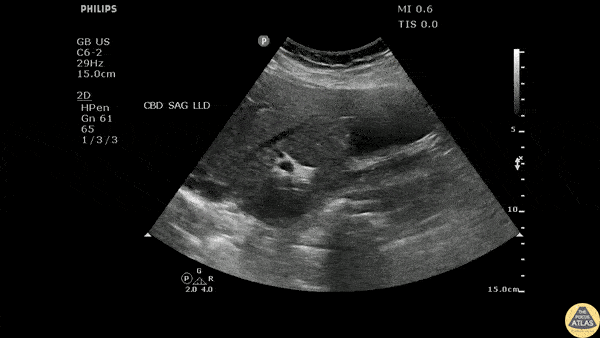

Longitudinal view of the gallbladder revealing two unique findings. A hyperechoic structure with posterior acoustic shadowing indicative of a stone is located in the neck. Two smaller hyperechoic structures can be seen attached to the wall of the GB body, likely adenomyomatosis. Image courtesy of Robert Jones DO, FACEP @RJonesSonoEM Director, Emergency Ultrasound; MetroHealth Medical Center; Professor, Case Western Reserve Medical School, Cleveland, OH View his original post here